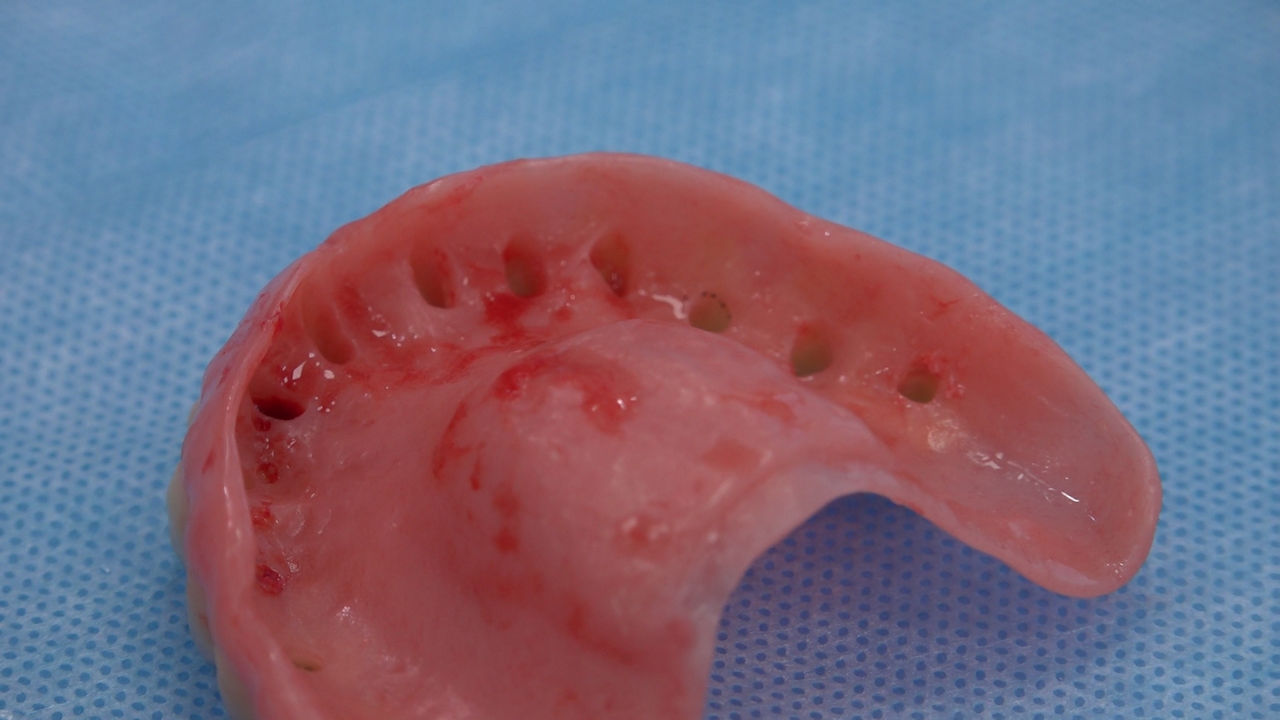

Practiculum Implantologii to szkolenie dla adeptów implantologii zorientowane na praktyczne opanowanie procedur zabiegowych i wprowadzenie implantologii do własnej praktyki. Dla Kursantów Grupy A, X Sezonu, 9 Sesja stanowiła ostateczny sprawdzian umiejętności zabiegowych zdobytych podczas procedur wykonywanych w trakcie szkolenia pod kierunkiem dr n.med. Violetty Szycik i dr Małgorzaty Piotrowskiej. Zobacz więcej na: www.practiculum.pl